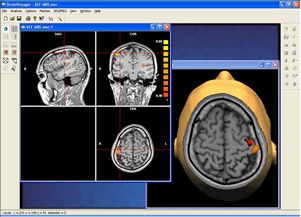

Parametric and non-parametric statistical maps may be superimposed both on the original functional scans as well as onto T1-weighted 2D or 3D anatomical reference scans. Time courses of selected regions-of-interest (ROIs) are available both in 2D and 3D representations. Statistical maps may be computed either in the 2D or 3D representation since structural as well as functional 4D data (space x time) are transformed into Talairach space. This allows you to compare activated brain regions across different experiments and across different subjects

Segmentation of tissue (e.g., isolating the brain, differentiating gray and white matter) is performed using region-growing methods, filter operations as well as the application of 3D templates. Using the mouse it is very easy to explore a 3D volume with superimposed pseudocolor-coded statistical maps in a four-window representation showing a sagittal, coronal, transversal and oblique section. Based on a (segmented) 3D data set a three-dimensional reconstruction of the subjects' head and brain can be calculated and displayed from any specified viewpoint using volume or surface rendering.

Volume rendering is performed with a very fast ray casting algorithm; lightning calculations are based on Phong-shading. Surface rendering of reconstructed surfaces is performed using OpenGL. Using texture mapping, a reconstructed surface (e.g., head or brain) may be sliced in real time, showing both surface and volume data at the same time. Initial polygon meshes serve as the basis for surface finding, cortex inflation and cortex flattening computations.